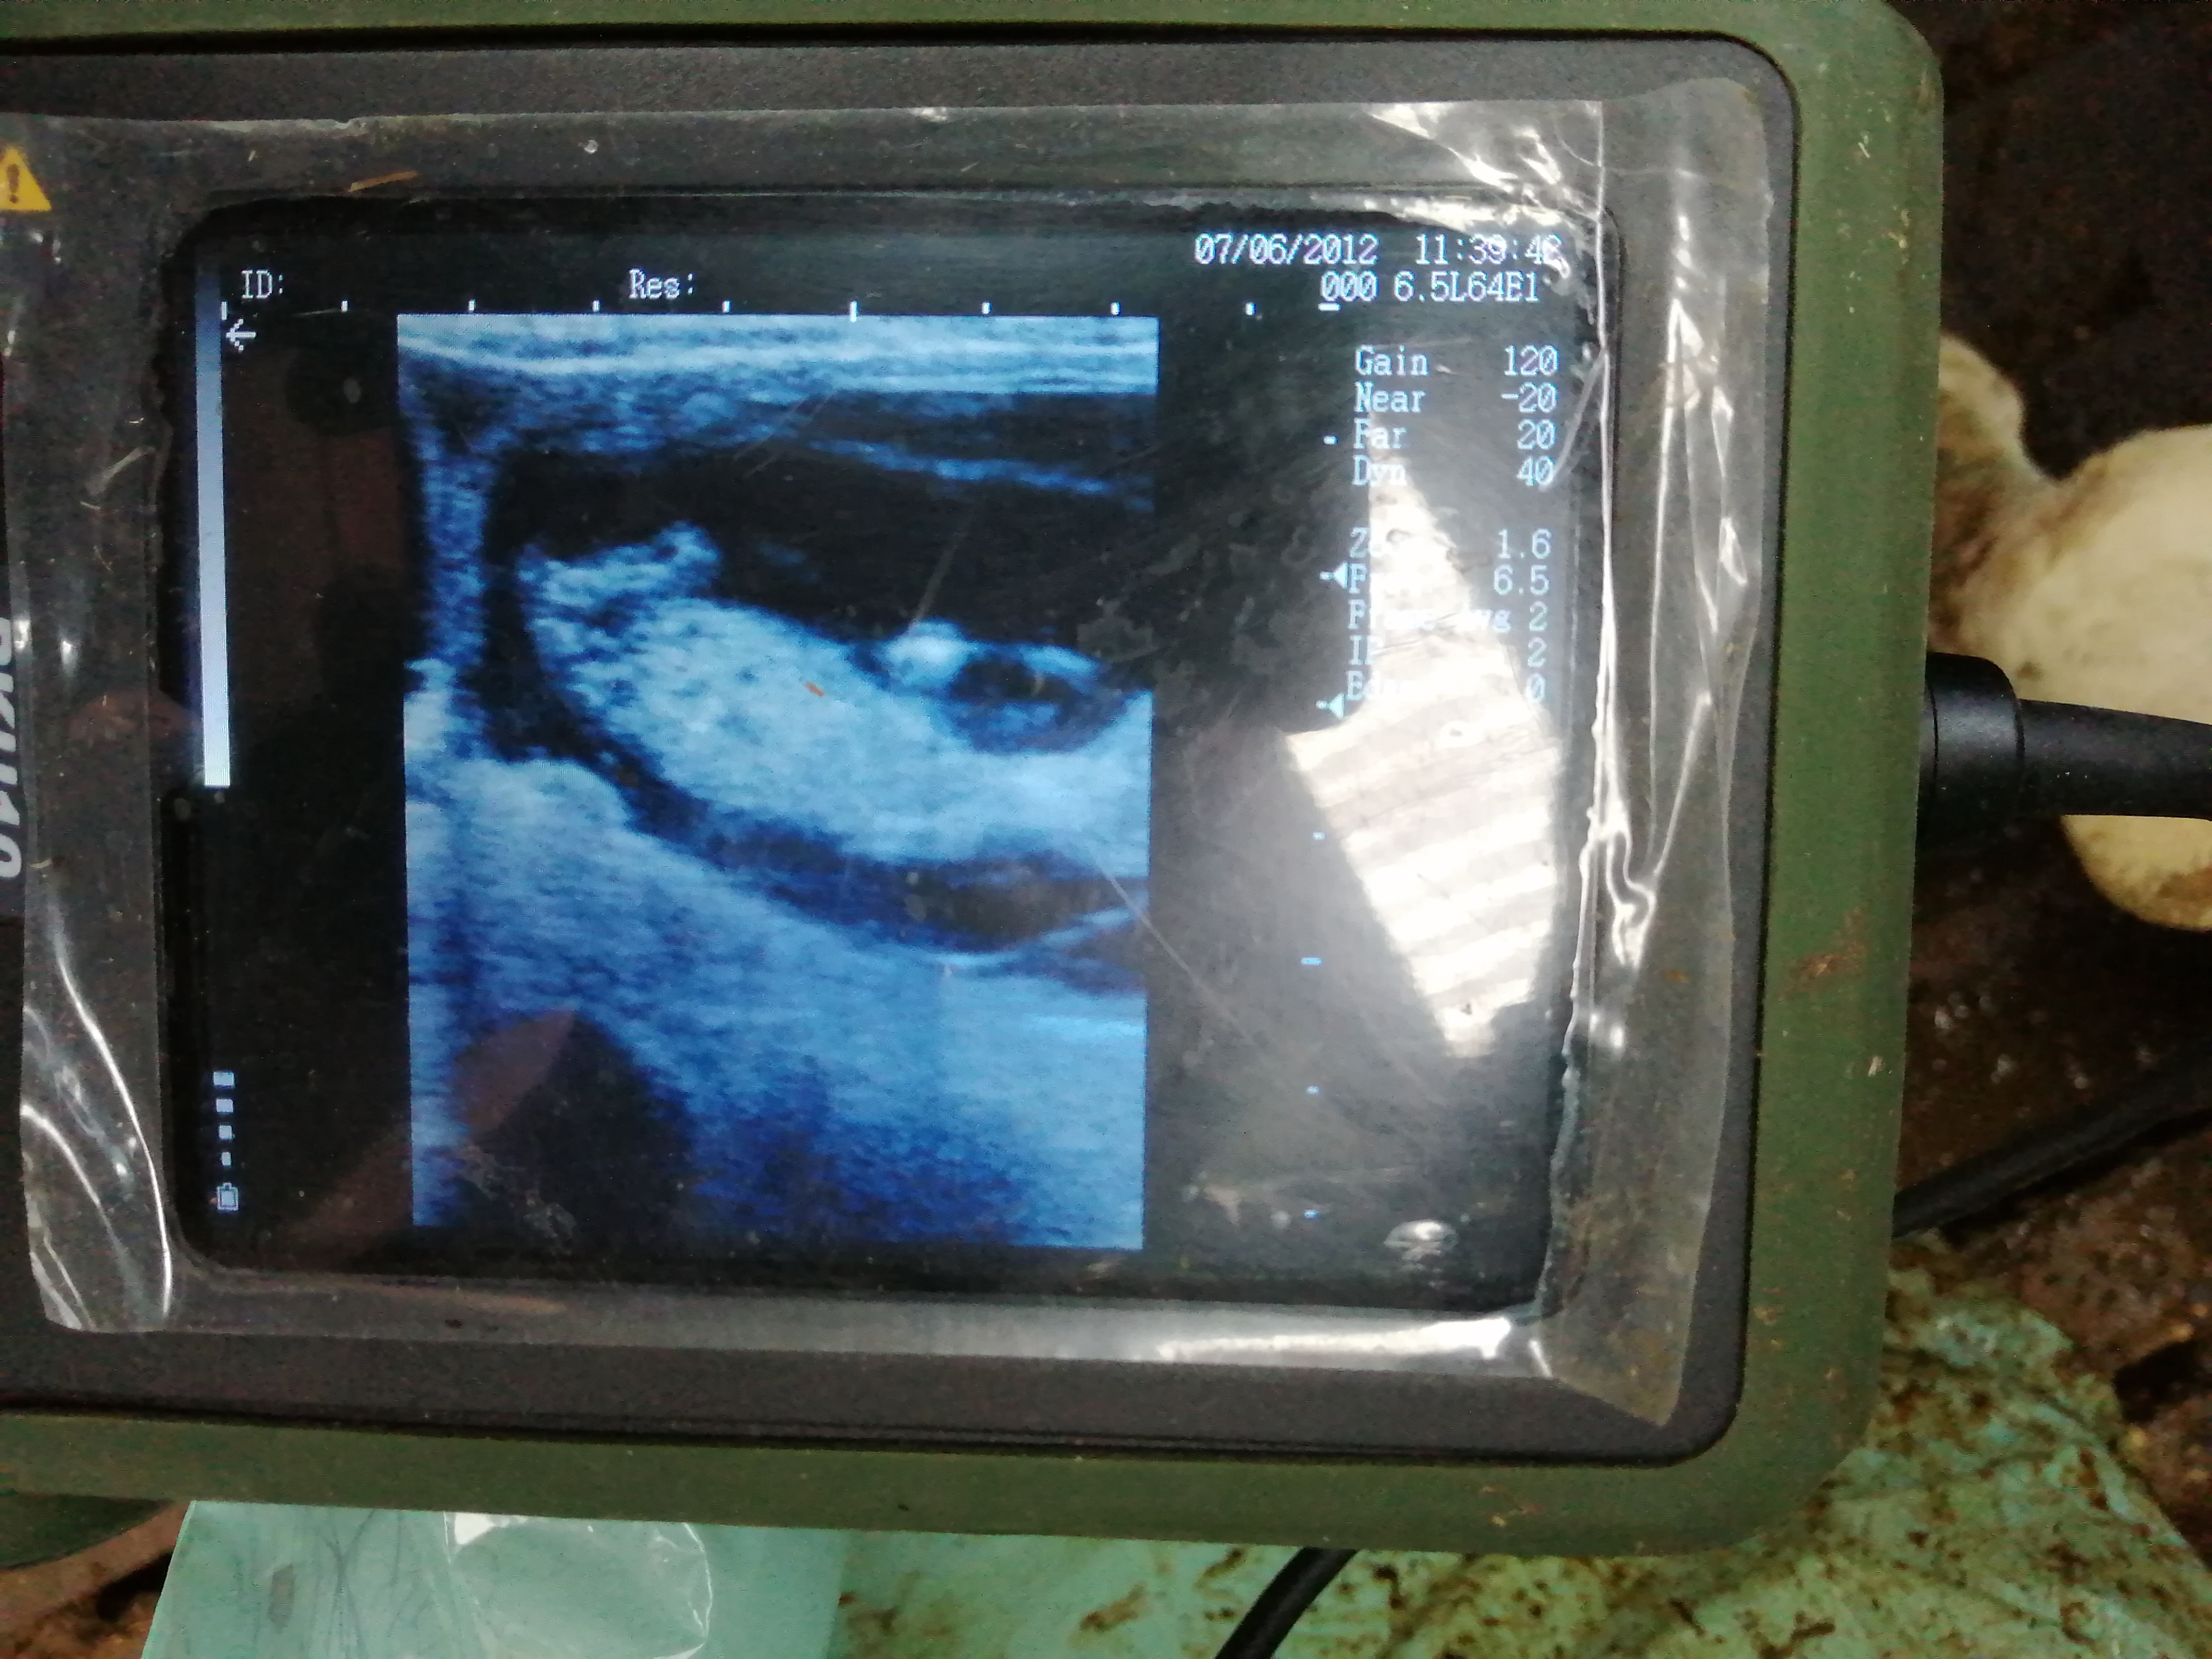

Koeien die ongeveer 30 dagen geleden en meer geïnsemineerd zijn, laat ik controleren op dracht. Ik kan zelf al zien via de activiteitsmeting op de computer of een koe na 3 weken (vruchtbaarheidscyclus) terug tochtig wordt. Maar door met de scanner de dracht te controleren, weet ik zeker dat een koe drachtig is (“vol” zoals we zeggen) of niet (“leeg”). Hieronder een prachtige echografie van een embryo van 60 dagen.

Het gebeurt niet veel dat hij zo mooi kan getoond worden met de scanner. Je ziet mooi het achterwerk en de achterpootjes van het kleine kalfje. Hier is het nog maar een paar centimeters groot, maar uiteindelijk wordt het geboren met een gewicht van zo’n 40 tot 50 kg.

Hierboven zie je de vorm van het kalfje ook al vrij goed: het kopje rechts, links daarvan het lijfje en de pootjes bovenaan. Het is altijd super als we zoiets zien verschijnen! Indien de drachtcontrole negatief is, moet de koe terug tochtig (gespoten) worden, waarna ze kan geïnsemineerd of gedekt worden. Negen maanden na een geslaagde inseminatie of dek wordt het kalfje dan geboren!